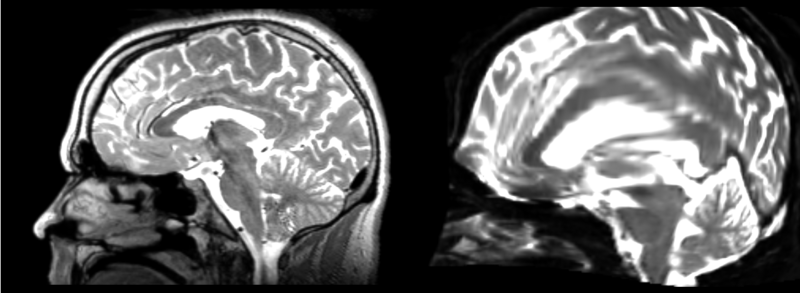

Registration of a DTI baseline image to corresponding realigned t2 iamge via the BSpline selection in the Register Images module.

current15:13, 21 April 2009Thumbnail for version as of 15:13, 21 April 20091,162 × 426 (348 KB)Rauscha (talk | contribs)Registration of a DTI baseline image to corresponding realigned t2 iamge via the BSpline selection in the Register Images module.